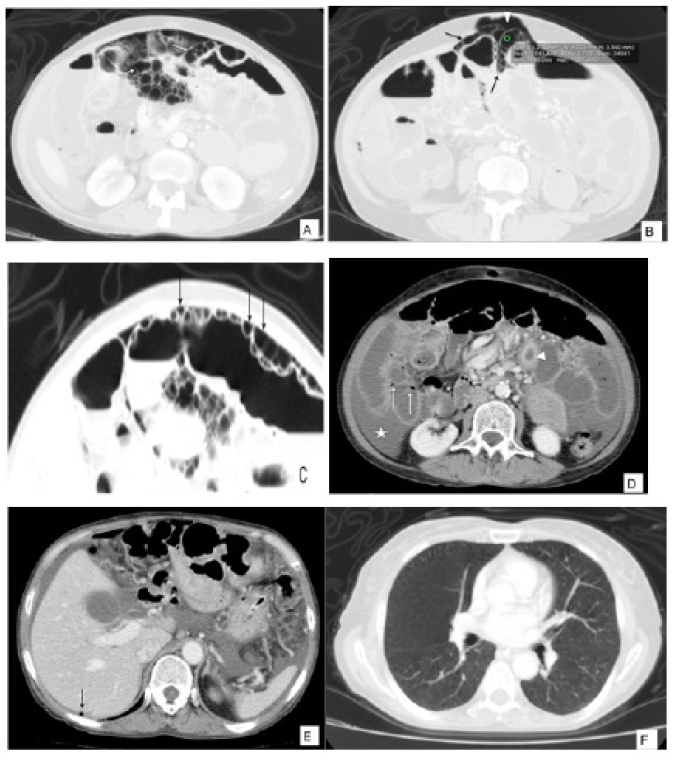

Ante la poca mejoría de los síntomas con el tratamiento médico se solicitó tomografía de abdomen (figura 1) en la que se observaron múltiples imágenes quísticas, redondeadas, localizadas en la pared del intestino delgado asociadas a ligero engrosamiento parietal del yeyuno, neumoperitoneo y líquido libre intra-abdominal. No se visualizaron alteraciones de las estructuras vasculares, pileflebitis ni neumobilia.

Se trataba de una mujer de 66 años sin antecedentes personales relevantes y quien consultó por un dolor abdominal difuso sin otros síntomas asociados. Al examen físico no se encontraron signos de irritación peritoneal. Se solicitó tomografía de abdomen contrastado en la que se identificaron múltiples imágenes hipodensas con unidades hounsfield (UH) promedio de -967, con morfología circular y lineal comprometiendo la pared del colon transverso (figura 2). No se observó aire en la vena porta, neumoperitoneo ni otras complicaciones. Se le realizó colonoscopia la cual no encontró anormalidades. La paciente fue manejada de forma expectante con mejoría de su cuadro clínico, por lo que se realizó el diagnóstico de neumatosis quística.

El patrón que más se ha asociado a enfermedad benigna es el patrón circular (quístico) 2,7,8, el cual es mas común en el colon y está descrito en neumatosis intestinal quística 2,9,14. Por el contrario, el patrón lineal fue descrito por Kernagis et al. cuando ocurre infarto transmural 2 (figura 3) y está relacionado en el tipo secundario 7. El patrón curvilíneo también se ha relacionado mas con formas severas 8.